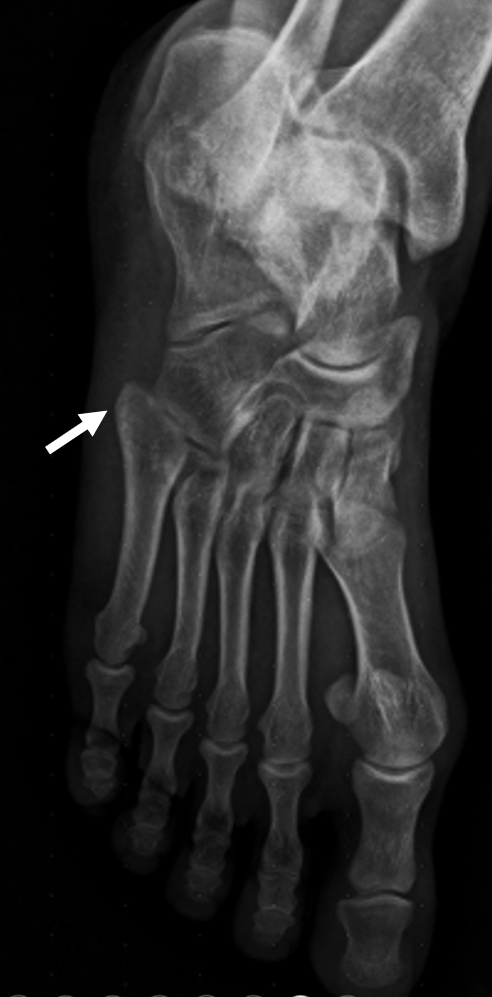

A 29-year-old man presented to the emergency department with pain in the 5th metatarsal following an ankle sprain.

A foot radiograph revealed a suspicious radiolucency at the base of the 5th metatarsal (zone I). CT demonstrated a subtle fracture line on axial slices (indicated by white arrows). On reformatted sagittal and coronal planes, the non-displaced fracture line was clearly visible (white arrows), consistent with a pseudo-Jones fracture. Because the fracture can appear equivocal on plain radiographs and axial CT slices, long-axis reconstructions are essential for accurate evaluation in trauma patients.

Avulsion fractures of the 5th metatarsal tuberosity or styloid (pseudo-Jones fractures) are the most common foot avulsion injuries, accounting for more than 90% of fractures involving the base of the 5th metatarsal (zone I). True Jones fractures occur at the metaphyseal–diaphyseal junction (zone II, yellow), while stress fractures typically arise in the proximal diaphysis (zone III, blue).

Pseudo-Jones fractures typically appear as a transverse or oblique radiolucent line at the base of the 5th metatarsal tuberosity (zone I, purple), often associated with cortical step-off or minimal displacement. On plain radiographs, they may be subtle and can be obscured by overlapping structures, leading to underdiagnosis. CT, particularly with multiplanar reformations, improves detection by delineating the fracture line and ruling out intra-articular extension. MRI is not routinely required but can demonstrate associated marrow edema when the fracture is radiographically occult. Importantly, differentiation from true Jones fractures, which occur at the metaphyseal–diaphyseal junction (zone II, yellow), and stress fractures, typically arising in the proximal diaphysis (zone III, blue), is crucial, as treatment strategies and healing potential vary significantly between these entities.